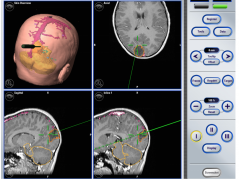

胶质母细胞瘤(GBM)是成人常见的恶性脑肿瘤,许多在较初治疗后几个月内复发,并在2年内出现致命进展。在使用5-氨基乙酰丙酸的荧光、神经导航和术中磁...

小儿丘脑肿瘤常被认为是无法手术的。但是,现代显微外科技术以及神经影像学的改进使得能够进行准确的术前计划,可以以更顺利的方式进行切除...